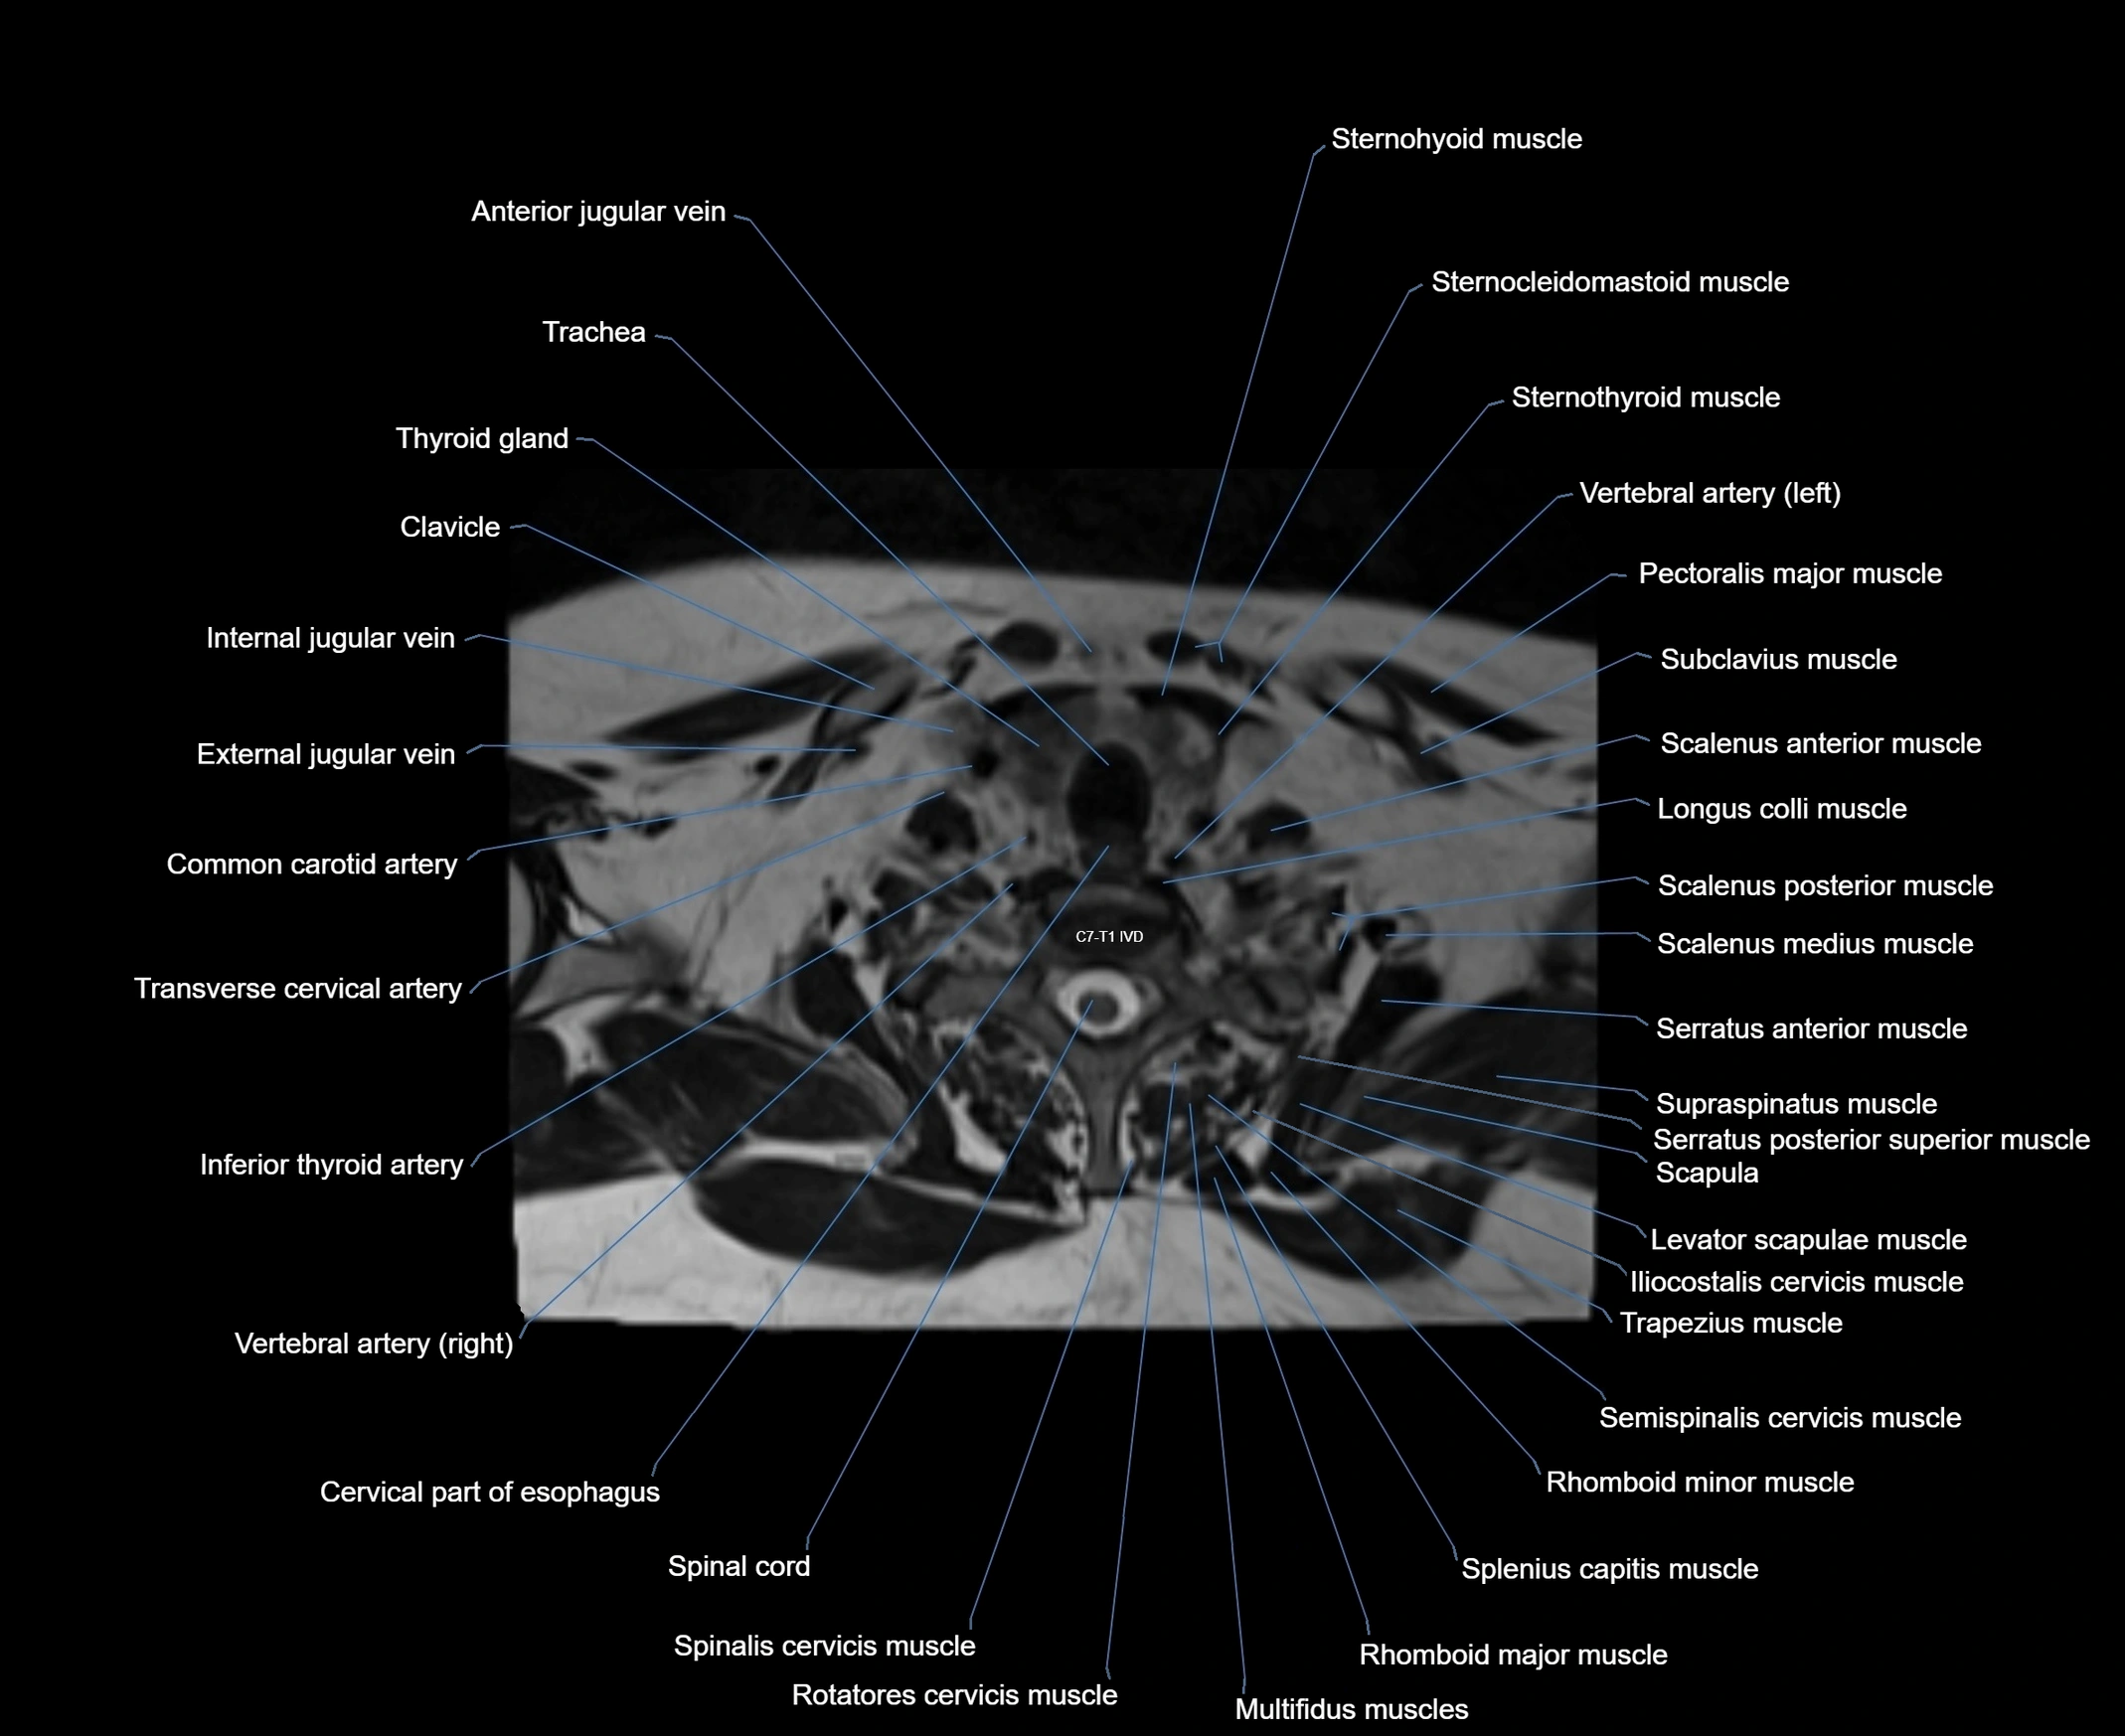

- Anterior jugular vein

- Cervical part of esophagus

- Clavicle

- Common carotid artery

- External jugular vein

- Iliocostalis cervicis muscle

- Inferior thyroid artery

- Levator scapulae muscle

- Longus colli muscle

- Multifidus muscles

- Pectoralis major muscle

- Rhomboid major muscle

- Rhomboid minor muscle

- Rotatores cervicis muscle

- Semispinalis cervicis muscle

- Serratus anterior muscle

- Serratus posterior superior muscle

- Spinal cord

- Spinalis cervicis muscle

- Spinous process of vertebra

- Splenius capitis muscle

- Sternohyoid muscle

- Sternothyroid muscle

- Subclavius muscle

- Supraspinatus muscle

- Trachea

- Transverse cervical artery

- Trapezius muscle